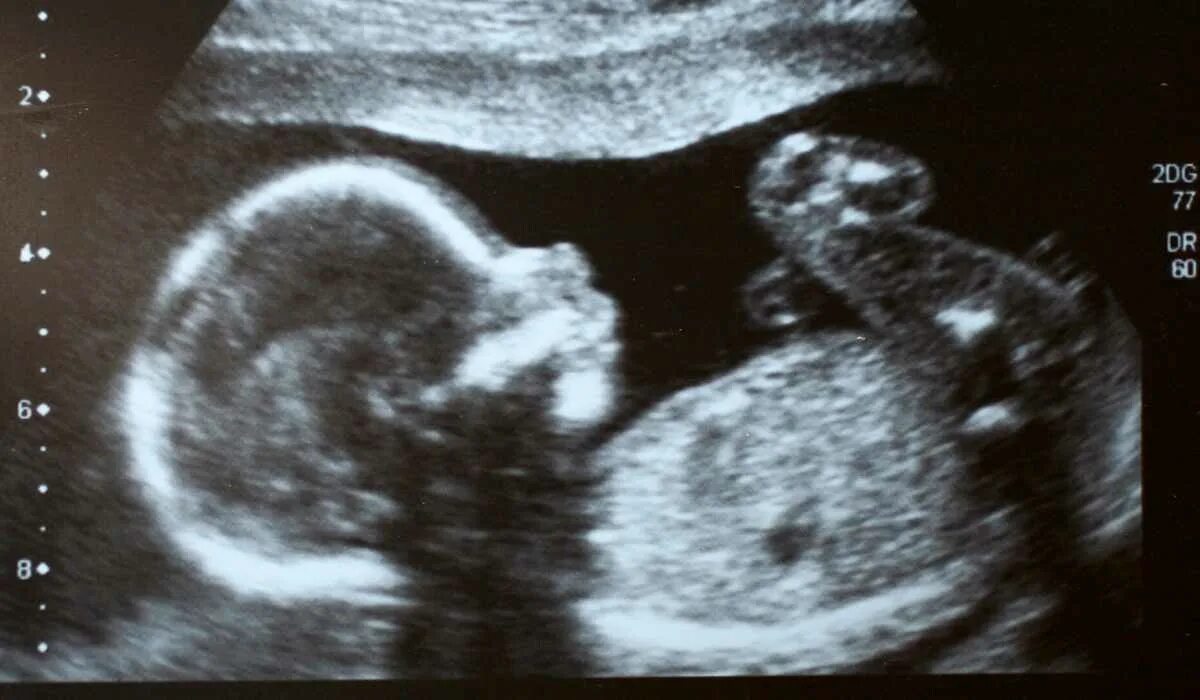

Ребенок в животе 22 недели